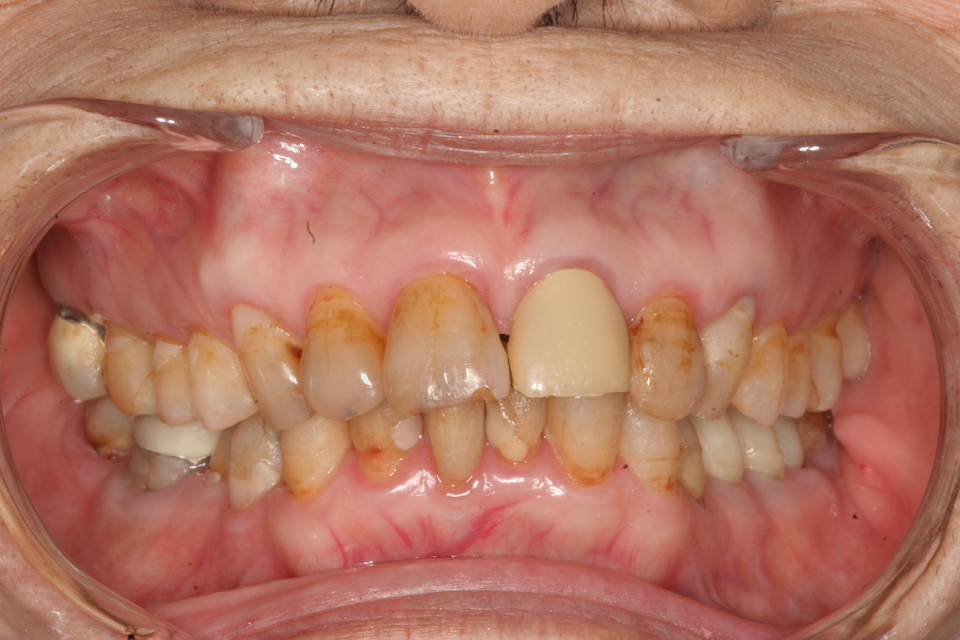

84歳

3年毎の画像を遡って見てみましょう。